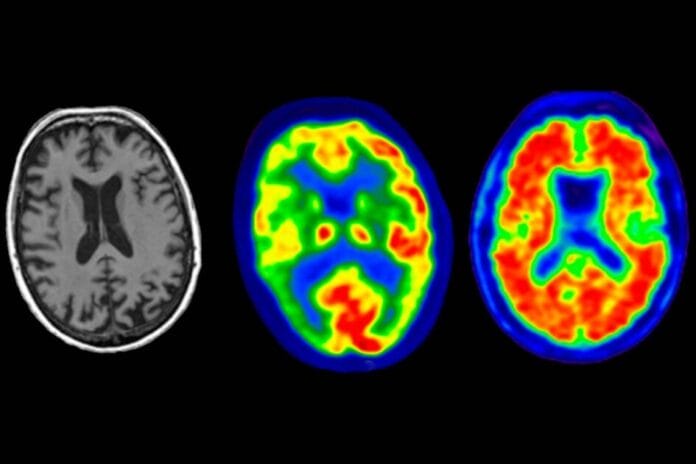

El litio se produce de forma natural en el cerebro, lo protege de la neurodegeneración y mantiene la función normal de todos los tipos principales de células cerebrales, según un estudio que constata que la pérdida de este elemento es uno de los primeros cambios que conducen al alzhéimer.